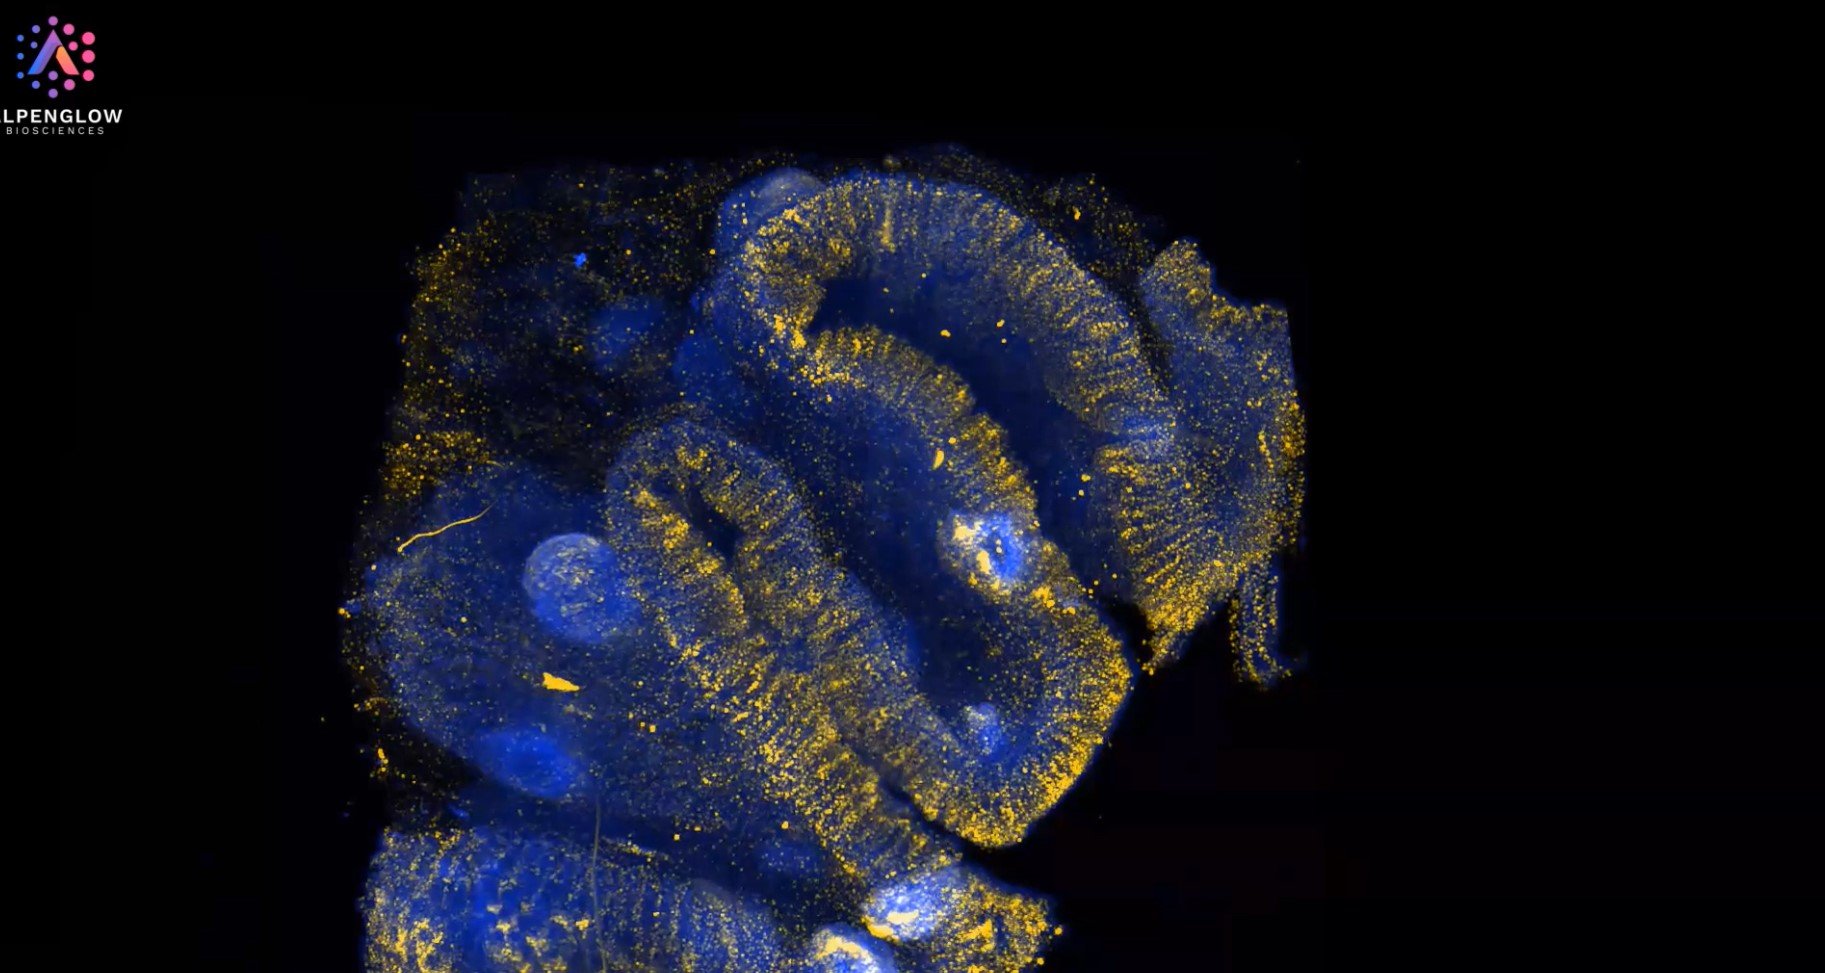

3D view of Human Normal Adjacent Colorectal Cancer

Explore this cutting-edge 3D imaging of Human Normal Adjacent Colorectal Cancer